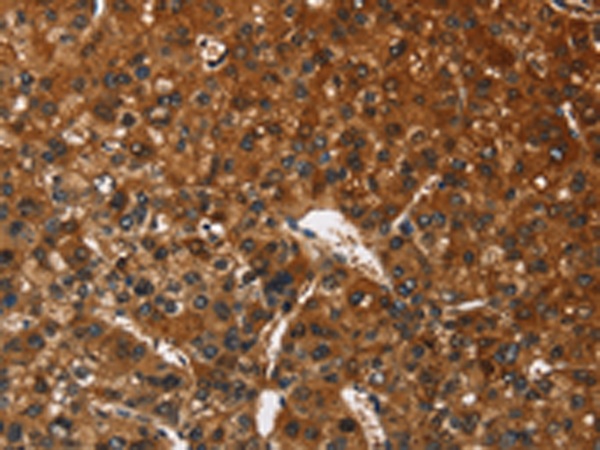

分类: 科研抗体货号: P08090别名: BIgR; NECL1; TSLL1; IGSF4B; Necl-1; synCAM3应用: IHC反应种属: Human, Mouse, Rat

分类: 科研抗体货号: P08109别名: SPGF7; CATSPER应用: IHC反应种属: Human

分类: 科研抗体货号: P08125别名: OX2R; MOX2R; CD200R; HCRTR2应用: IHC反应种属: Human

分类: 科研抗体货号: P08108别名:应用: WB,IHC反应种属: Human, Mouse, Rat